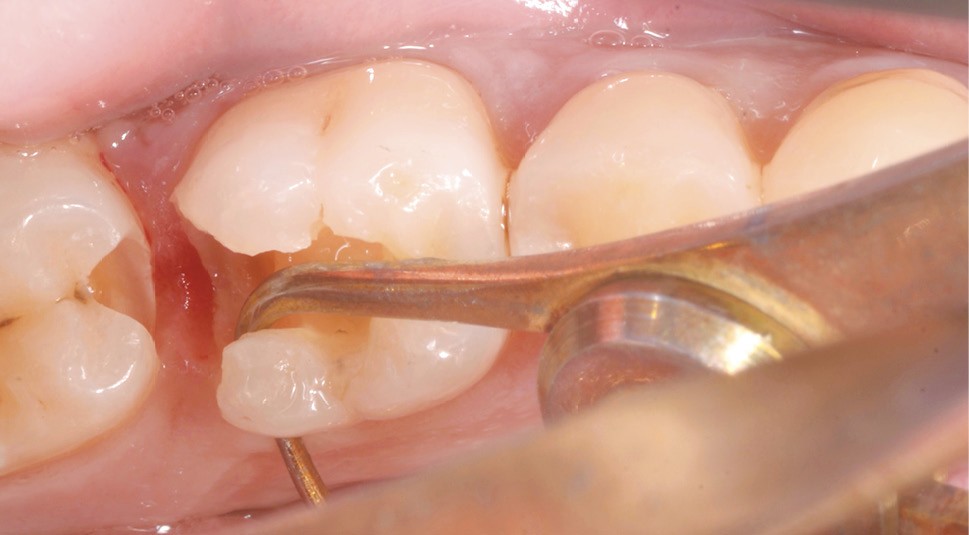

La localisation (type de dent)

Le pronostic clinique semble plus favorable pour les prémolaires que pour les molaires [3-5], car une plus grande résistance est généralement nécessaire pour les parois des molaires. Mais si 75 % des fractures à la mandibule affectent les molaires, et plus particulièrement la première molaire, au maxillaire, les fractures se répartissent équitablement entre le secteur molaire et le secteur prémolaire [6]. L’épaisseur de l’émail, la largeur de la cuspide comme les…